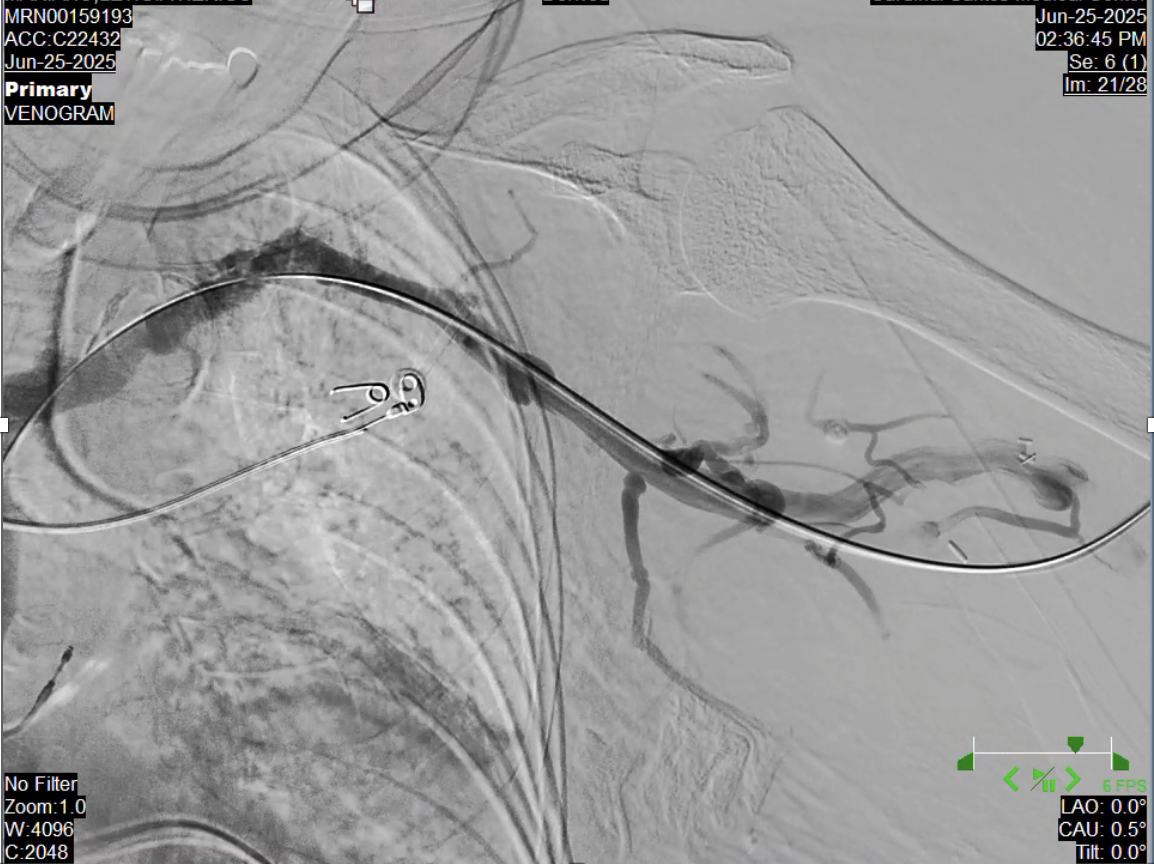

Digital subtraction venography revealed near total occlusion of the left subclavian vein at the level of the first rib wherein measurements taken on the lesion which was noted 90-95% stenosis. Multiple venous collateral formation with faint and sluggish antegrade collateral flow distal to the stenosis.

Left brachioaxillary graft was accessed using a Fr 4 hemostatic sheath. Venography done showing stenosis at the left subclavian vein at the level of the first rib. Mesurements taken with a degree of stenosis more than 95%. A balloon catheter was deployed using 10.0 x 40.0 mm Armada Abbott Catheter inflated at 10 atm for 30 seconds with gradual resolution of stenosis. Post venoplasty shots revealed normal contrast flow with disappearance of venous collaterals. No intraprocedural complications noted.